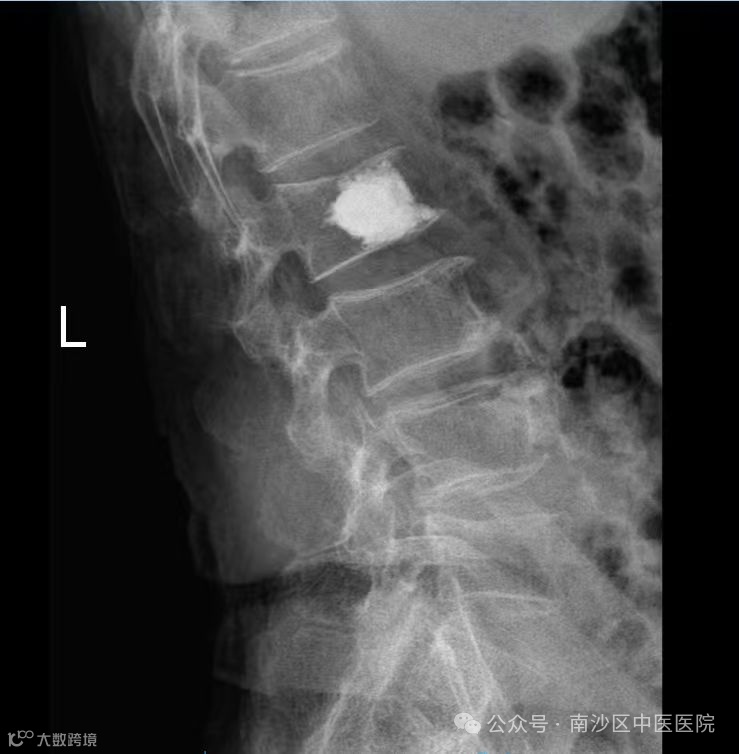

术前

张婆婆患有骨质疏松,此前因不慎滑倒,导致腰背部剧烈疼痛,无法自主翻身。经检查,诊断为腰2椎体压缩性骨折,椎体被压缩了近1/2。考虑到患者高龄、身体状况与恢复需求,珠江院区外科团队为其制定了经皮穿刺椎体成形术的治疗方案。

手术在X光引导下进行,通过背部约3毫米的穿刺口,将穿刺针精准置入骨折椎体。手术历时约30分钟,出血极少。